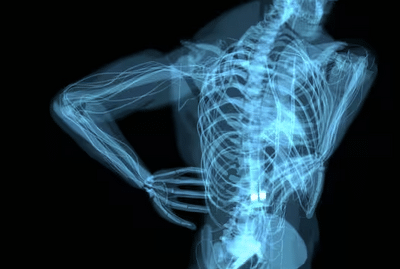

Spinal: The spine plays a vital role in the human body. It hinders the human body's balance and mobility. Let us explain what problems it can cause.

Spine fracture recovery: World Spine Day is celebrated every year on October 16th. The purpose behind this day is to raise awareness about the importance of the spine and the diseases associated with it. The spine is the support that provides balance and movement to the entire body. Any problem with the spine directly impacts the body, sometimes making it difficult for people to live a normal life. Many people take this lightly, but taking back pain or a spine problem lightly, but taking them lightly can prove costly later. Let us explain why and how.

People often wonder whether the spinal cord can rejoin once it's broken. Experts say there's a possibility, but this depends entirely on the location and severity of the injury. For example, if the fracture is minor, it can heal with rest, physiotherapy, and medication. In severe cases, when bone fragments are pressing on the spinal cord, surgery may be required. However, it's important to note that if the spinal cord is severely damaged, it may not function normally again. Patients may find it difficult to move around normally, or they may even become permanently paralyzed.